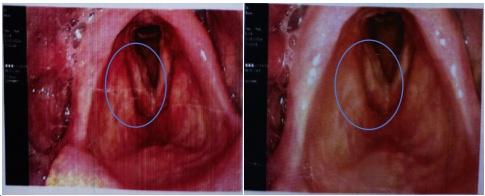

治疗前肿瘤(红色区域)

龙山院区肿瘤科吕杨、何宜生两位主治医师,在组长鲍亮亮副主任医师的带领下,对涂爷爷的病情进行了准确细致的评估,制定了个性化的治疗方案。经过精准的定位、细致的靶区勾画,多次的计划优化后,确定了针对患者喉部肿瘤的根治性放疗方案。当患者放疗过程中出现放射性咽喉炎,咽喉疼痛明显,影响进食时,又及时进行了个体化的营养评估和营养干预,避免了放疗导致的营养不良。放疗结束后,涂爷爷的声音嘶哑症状基本缓解,喉镜检查肿瘤完全消失,体重保持稳定,并没有因抗肿瘤治疗而更加虚弱。这让涂爷爷和家人深感欣慰,也坚定了他们继续治疗的信心。

治疗后肿瘤消失(蓝色区域)